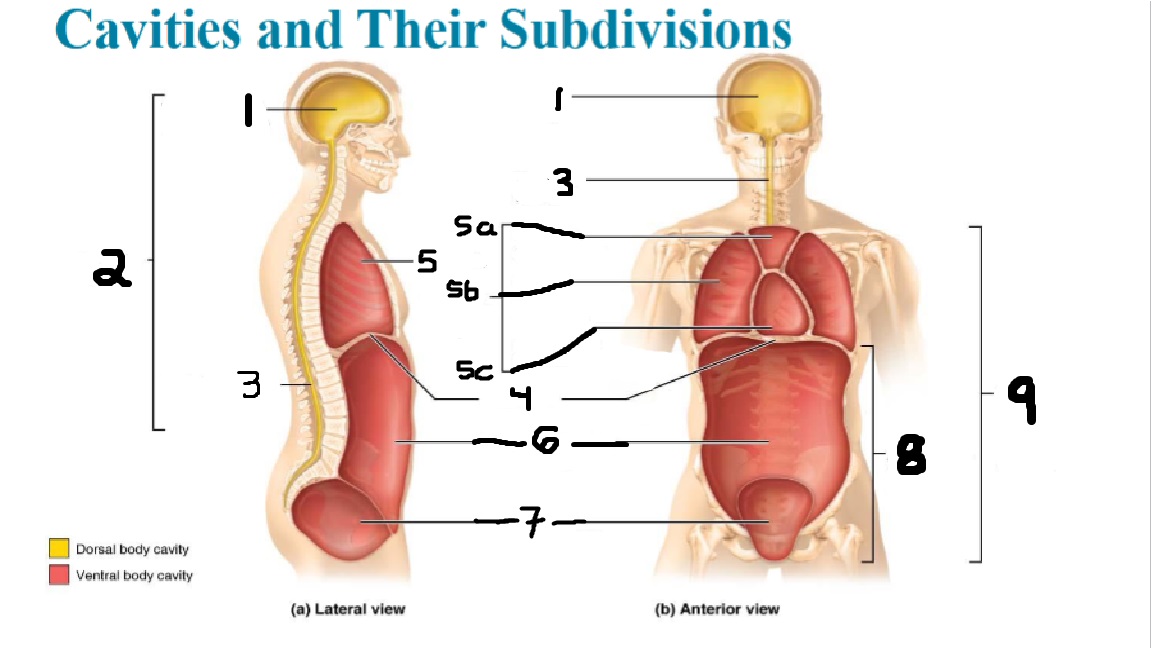

What cavities are part of the dorsal cavity?

The cranial and the Spinal (vertebral) cavities

What kind of cavity is labeled 2?

The dorsal body cavity (containing the cranial and spinal cavities)

What is the purpose of the dorsal cavity?

protects the nervous system

What is the main organ encased by the cranial cavity?

the brain

What cavity is labeled #1?

The cranial cavity

What is the main organ encased by the vertebral cavity?

the spinal cord

What is another word for the vertebral cavity?

the spinal cavity, or the spinal canal

What body cavity is labeled 3?

the vertebral cavity.

What cavities are included in the ventral cavity?

the thoracic, abdominal, and pelvic cavities.

What body cavity is labeled #6?

the abdominal cavity.

What are the main organs of the abdominal cavity?

the digestive organs such as the stomach, intestines, spleen and liver

What cavities are included in the Abdominopelvic cavity?

the abdominal cavity and the pelvic cavity

What body cavity is labeled #8?

The Abdominopelvic cavity

What does the diaphragm separate?

the thoracic and the abdominal cavities

What is labeled #4?

the diaphragm

What organs does the pelvic body cavity contain?

urinary/reproductive organs and rectum

What is labeled #7?

the pelvic cavity

What does the thoracic cavity encase?

the heart and the lungs

What is labeled #5?

the thoracic cavity

What part of the thoracic body cavity is labeled 5a?

superior mediastinum

What part of the thoracic body cavity is labeled 5b?

pleural cavity

What part of the thoracic body cavity is labeled 5c?

pericardial cavity within the mediastinum

What body cavity encloses the heart?

the pericardial cavity.